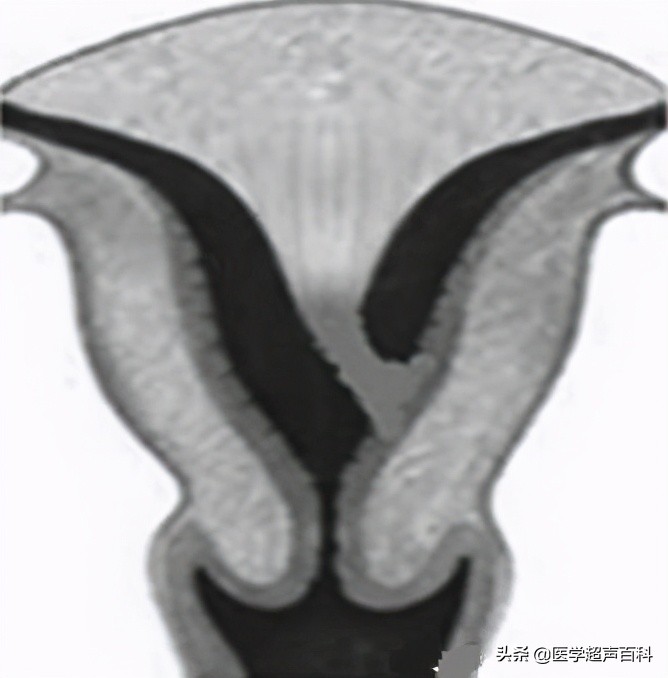

6.纵膈子宫:子宫大小外形正常,宫底横泾较宽,三维超声冠状面内膜呈“V”形为完全纵膈,呈“Y”形为不完全纵膈。